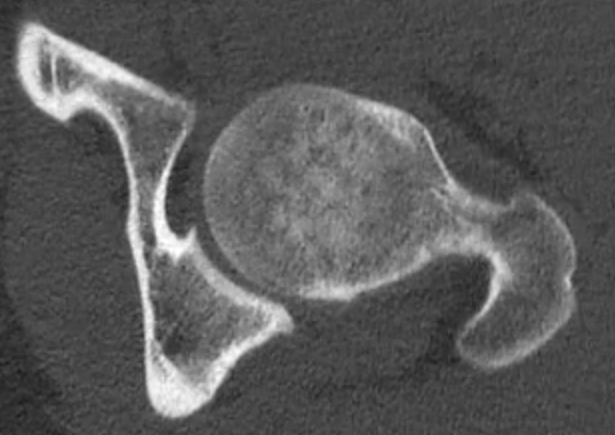

CT

Pincer

Focal pincer

Os acetabuli

Pincer impingement

a. Global

- overcoverage of femoral head

- profunda, protrusio

- acetabular retroversion / relative anterior rim overcoverage

b. focal

- os acetabuli

- focal acetabular lesion